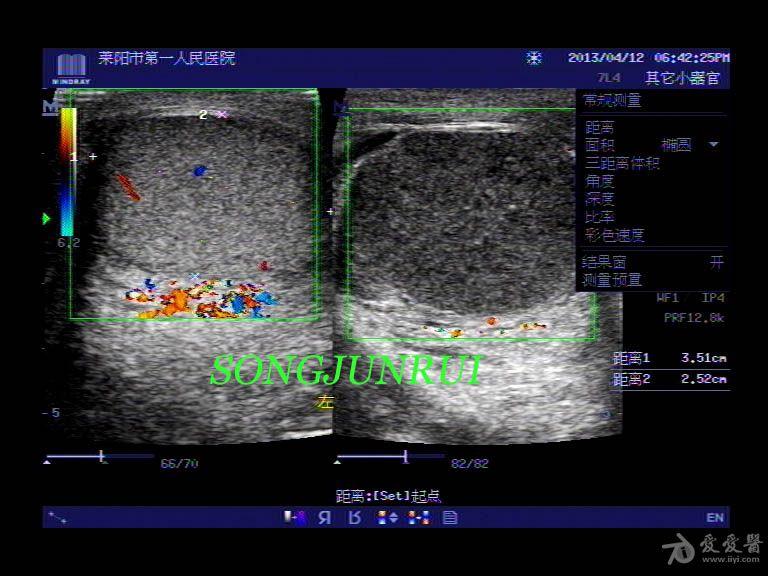

睾丸超声图

睾丸超声图,

急性睾丸附睾扭转-临床超声诊断学-医学

睾丸恶性肿瘤的超声诊断

睾丸扭转 超声医学讨论版 爱爱医医学论坛 爱爱医医学网

睾丸内无回声是什么 超声医学资源版 爱爱医医学论坛 爱爱医

超声入门贴56睾丸扭转